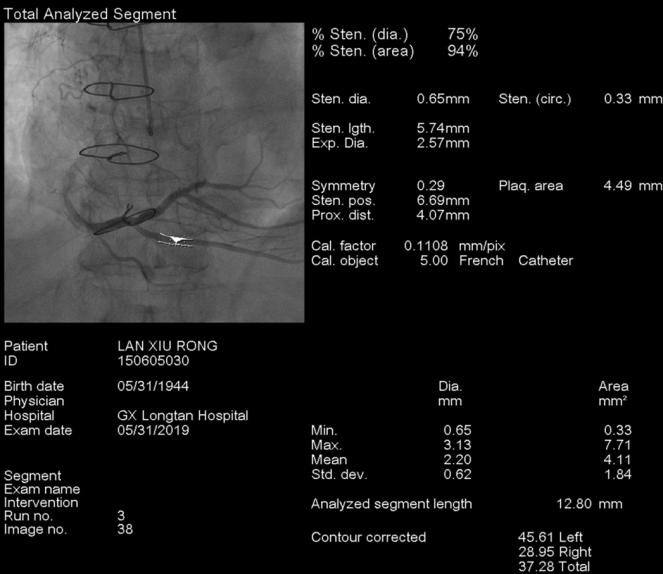

图2、3. 术前和术前测量

据悉,该患者10年前曾经行心包剥脱术,出现阵发性胸痛症状后到我院就诊,冠脉造影提示右冠状动脉狭窄80%。在详细了解情况后,心血管内科专家与影像专家进行了会诊,为患者确定了周密的治疗计划和手术方案。